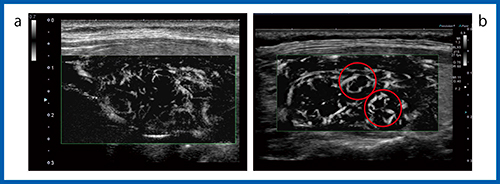

24MHz超高周波リニアプローブ

Aplio i800の新しいリニアプローブ「PLI-2004BX」は,8〜24MHzに対応した超高周波プローブである。24MHzの高周波によって,体表に近い部分から深部まで高分解能の画像が得られる(図11 b)。通常の周波数で見た甲状腺では,囊胞(↓)が確認できるが,胸壁に近い部分にはなにも見つからない(図11 a)。しかし,24MHzの超高周波で観察すると,胸壁に近い部分に小さな囊胞(↑)が確認できる。超高周波プローブを使うことで,胸部の浅い領域の腫瘍やリンパ節など,より表在に近い領域の観察が可能になると考えられる。

図11 24MHz超高周波プローブ「PLI-2004BX」

a:10MHz(PLT-1005BT) b:24MHz